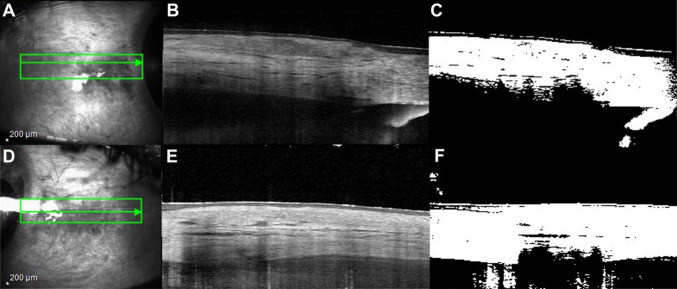

Results: Nine patients with median age of 52 ± 12.8 years were assessed. Eight patients were female. Rheumatoid arthritis and history of treated latent tuberculosis (33.3%) were the most common causes of anterior scleritis. Mean scleral thickness was 582.93 ± 124.03 µm and 648.59 ± 103.61 µm for violaceous sclera and the corresponding unaffected areas of the contralateral eye, respectively (mean difference = -65.65 µm, 95% CI: -143.73 to 12.42, p = 0.0885). The mean image contrast percentage of scleral hyperreflectivity as assessed by image conversion in an area of violaceous hue was 65.07 µm ± 6.49 µm compared to 42.70 µm ± 5.46 µm of unaffected areas (mean difference = 22.37 µm, 95% CI: 14.72 µm to 30.03 µm, p = 0.0001).

Conclusion: Using AS-OCT, the thicknesses of violaceous sclerae were not significantly thinner than the contralateral unaffected areas, despite a mean difference of approximately 65 microns. The increased scleral hyperreflectivity observed in the violaceous sclera may suggest collagen remodeling in these areas. Such remodeling could play a role in the sclera reflecting violaceous hues while still preventing direct visualization of the underlying choroid.